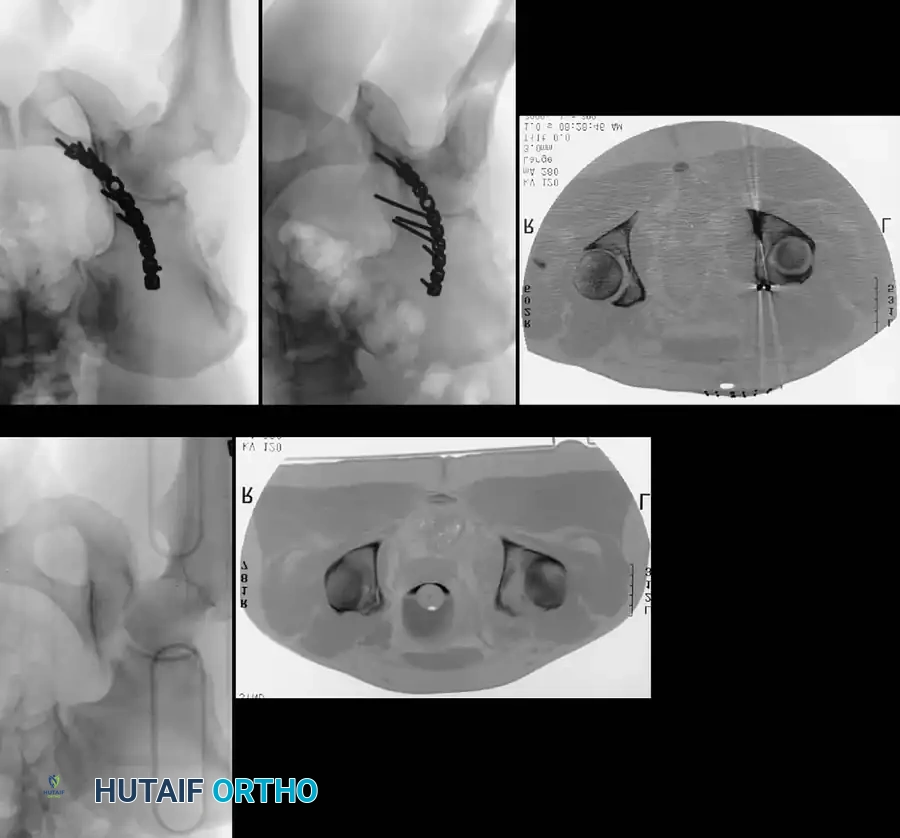

Associated Surgical & Radiographic Imaging

Hutaifortho's Orthopaedic Diagram